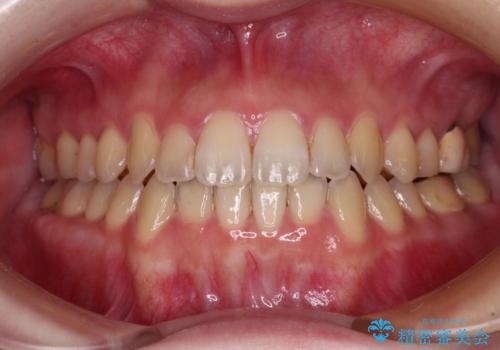

前歯をきれいにしたい インプラントや部分矯正を用いた総合歯科治療

- 抜歯の必要な前歯や、以前治療した前歯のクラウンの外観を気にして来院された患者様です。

処置を予定していた歯を仮歯に変えた時点で、下顎前歯の部分矯正を行うかどうかを尋ねたところ、折角なので行いたいと言うことでしたので、矯正治療を行うこととしました。